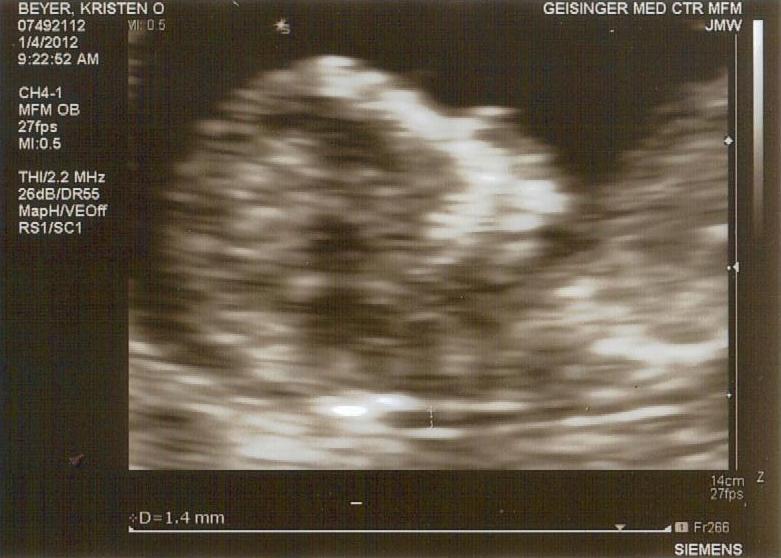

Last summer when Trafton was one year old, we saw the nephrologist again. This ultrasound showed that Trafton's one kidney was enlarged (again, good news) to the size of a seven-year-old's kidney. This was expected due to the need for overcompensation for the missing kidney. Everything looked good except the nephrologist noticed a small mass located on Trafton's bladder. When she looked back at the ultrasound from Trafton's birth, she saw that the mass was present but incorrectly labeled as the rectum. She called it a mesonephric duct cyst and said that it needed to be checked out by a urologist.

Which brings us to today and our trip to see the urologist, Dr. Sumfest. We first got another ultrasound done and Trafton was great! He was so cooperative throughout the procedure; it was wonderful! Then we saw Dr. Sumfest. He said that this mesonephric duct cyst was enlarged quite a bit from the ultrasound six months ago. His theory is that this mass is not a cyst at all, but actually a very, very small second kidney that is not functioning properly. While I was pregnant, one of the high risk doctors that we saw mentioned that a kidney remnant may be found after Trafton was born. None was ever found on subsequent ultrasounds. Because ultrasounds are not very detailed, Dr. Sumfest said that he would like an MRI done to confirm that this cyst is, in fact, a second kidney. During the MRI, Trafton would need what the doctor called heavy sedation so that he would be able to lie very still for up to 45 minutes. They would use propophol and Trafton would need to be able to breathe on his own. Dr. Sumfest assured us that he would be very closely monitored by the pediatric radiology department and that they are excellent. He said that many departments needed to approve this MRI, so although he put the order in for the MRI immediately, it may take up to one month for someone to call us and schedule it.

If, after this MRI, it can be confirmed that this cyst is a small kidney, and that it is being enlarged because small amounts of urine (he said maybe like one teaspoon per month) are being trapped inside of there, then the removal of this kidney would be necessary. I asked him how invasive of a procedure this would be and he stated that it was "extremely rare" and "pretty invasive because we are taking an organ out of a small child." Yikes. He said also that he is not concerned about cancer in any way at this time, because he does not believe it is a cyst. If the MRI confirms everything that he is thinking, the removal of this kidney would be necessary because as it grows larger, there is an increased chance of it causing all sorts of "serious infections."